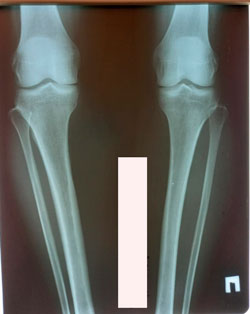

Исходник - 36 лет.

Дата операции - 12.01.2021